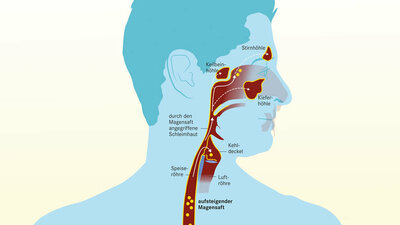

Refluxkrankheit: Wenn Magensäure in die Speiseröhre zurückfließt

Bei der Refluxkrankheit steigt regelmäßig Magensäure (rot dargestellt) in die Speiseröhre auf. Diesen Vorgang nennt man Reflux.

Die Symptome einer Refluxkrankheit verstärken sich oft im Liegen oder bei Druck auf den Bauch. Manche Menschen haben daher nachts vermehrt Beschwerden. Manchmal kommt es vor, dass Sodbrennen ausbleibt und sich bevorzugt Begleitsymptome wie Husten, Heiserkeit und Globusgefühl zeigen. Grund dafür ist ein stiller Reflux. Dabei steigt Magensäure direkt bis in den Rachen hoch.